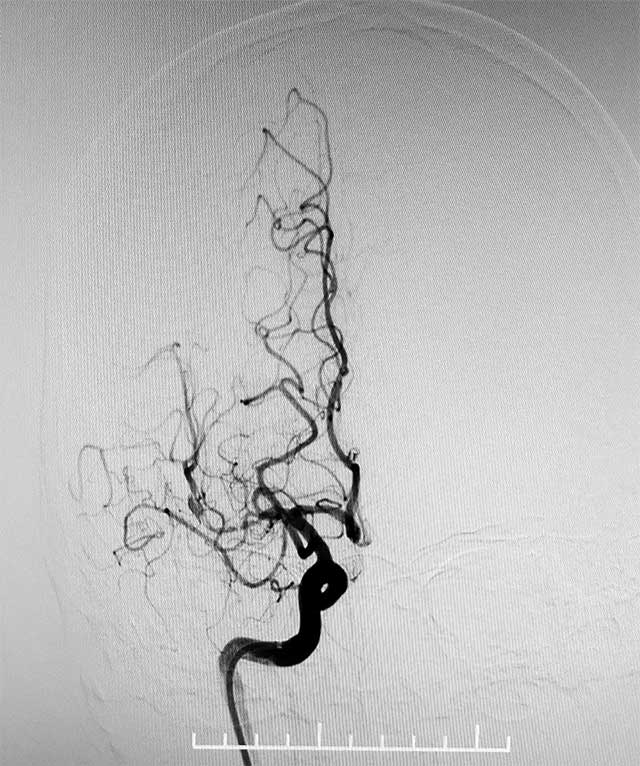

▲ 術(shù)前造影顯示,右側(cè)大腦中動(dòng)脈M1段閉塞

今年4月初,轉(zhuǎn)入上海藍(lán)十字腦科醫(yī)院,頭顱MRA提示右側(cè)大腦中動(dòng)脈M1段閉塞,遠(yuǎn)端分支減少,右側(cè)椎動(dòng)脈V4段纖細(xì)。隨后通過(guò)DSA(DSA是評(píng)價(jià)、診斷腦血管病的“金標(biāo)準(zhǔn)”,能夠提供血流的動(dòng)態(tài)信息,明確是否有其他血管進(jìn)行代償?shù)?進(jìn)一步評(píng)估顱內(nèi)血管的情況。DSA提示:右側(cè)大腦動(dòng)脈胚胎型,右側(cè)大腦中動(dòng)脈M1段閉塞。